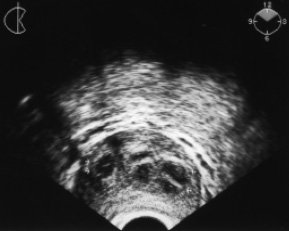

Эхографически формирование абсцесса предстательной железы включало две последовательные стадии - инфильтративную и гнойно-деструктивную. В инфильтративной стадии на фоне увеличения и отека предстательной железы абсцесс визуализировался как гипоэхогенный гомогенный очаг овальной или округлой формы диаметром от 0,5 до 1,5 см (в среднем 0,8 см) с нечеткими контурами и отсутствием реакции окружающих тканей предстательной железы (рис. 1). Выявлению фокусов инфильтрации помогало сопоставление их с эхогенностью неизмененных участков предстательной железы и парапростатической клетчатки. Клинические проявления заболевания в этой стадии были наиболее выражены.

Рис. 1. ТРУЗИ больного Т., 54 года. Абсцесс предстательной железы после трансуретральной резекции предстательной железы по поводу доброкачественной гиперплазии (начало заболевания). Жалобы на боль в промежности, учащенное болезненное мочеиспускание с резью. Гипертермия в течение 2 сут до 39°С с ознобом. В крови лейкоцитоз до 14x109; СОЭ 45 мм/ч. При пальцевом ректальном исследовании предстательная железа увеличена и резко болезненна, флюктуации нет. На поперечной эхограмме в обеих долях предстательной железы - формирующиеся абсцессы (указаны стрелками). Инфильтративная стадия заболевания.